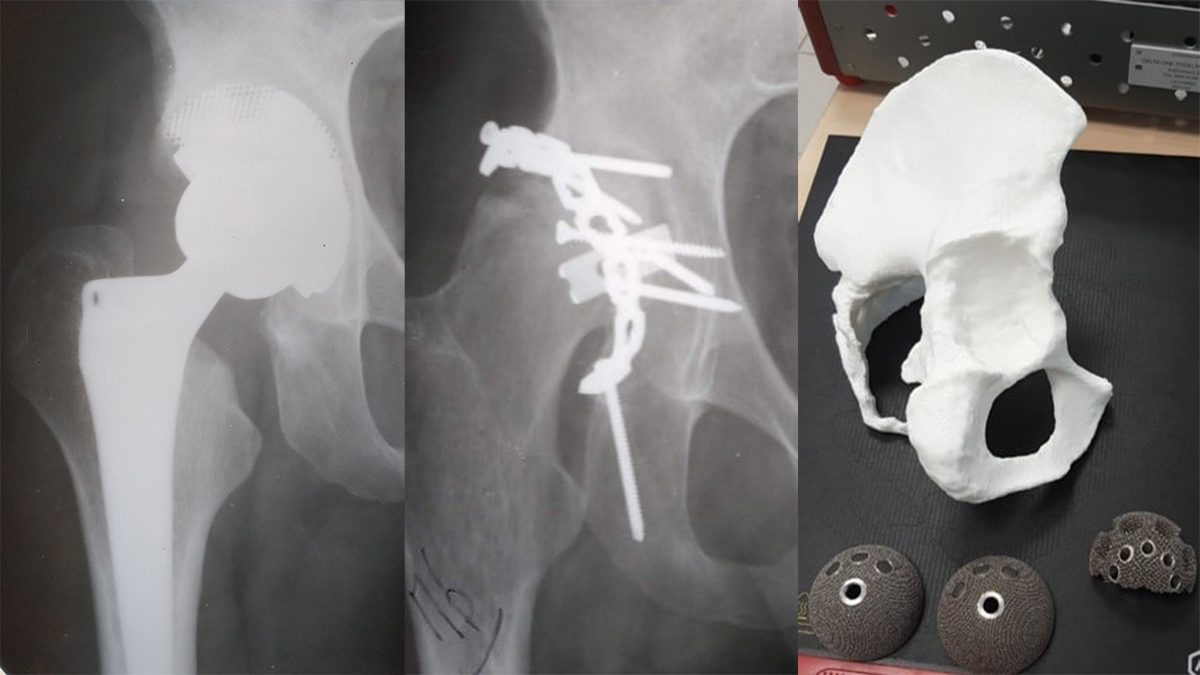

«У клініці ушкоджень Військово-медичного клінічного центру Західного регіону (м. Львів) вкотре непростий клінічний випадок — 24-річний пацієнт прооперований з приводу складного перелому вертлюгової западини і вивиху правого стегна. Переломи зрослися з частковим аваскулярним некрозом уламків та голівки стегнової кістки, що призвело до вкорочення кінцівки на 4 см і значного обмеження рухів. 3D-моделюванням підібрано індивідуальні імпланти для пацієнта (ендопротез Lima-TT з аугментом для заповнення кісткового дефекту). Результат — відновлення довжини кінцівки, обсягу рухів суглоба і повернення пацієнта до активного життя і праці» — таке коротке повідомлення нещодавно з’явилося на офіційній сторінці Facebook Військово-медичного клінічного центру Західного регіону.

— Ми забрали метал, який ставили раніше, некрози, рештки сполучної тканини, що там утворилася. Але у зв’язку з тим, що вертлюгова западина суглоба була деформована і не мала суцільної кулястої форми, а була з вибитим верхом, ми не могли використовувати стандартний ендопротез. Треба було встановлювати ендопротез зі спеціальною вставкою для заповнення дефекту кістки, що утворилася внаслідок аварії, — продовжив полковник медичної служби Дмитро Лось.

Щоб зробити індивідуальний ендопротез для пацієнта, військові лікарі за допомогою комп’ютерного томографа створили 3D-модель тазу. Потім виготовили її з пластику. Складна модель ендопротезу з аугментом вже підбиралася на 3D моделі тазу і абсолютно відповідала анатомічним особливостям пацієнта. Військові лікарі за рахунок наявної моделі ще до операції до дрібниць продумали, як правильно все поставити і припасувати.

— Операція тривала близько двох годин. З таким аугментом і 3D-моделюванням, у такому складному випадку — протезування проводили вперше. Але нам все вдалося! Пацієнт виписаний. Він може згинати ногу, повноцінно ходити, бо ми вирівняли у такий спосіб довжину ніг. А головне — він може продовжувати службу у Збройних Силах України, — констатує начальник клініки ушкоджень ВМКЦ Західного регіону полковник медичної служби Дмитро Лось.